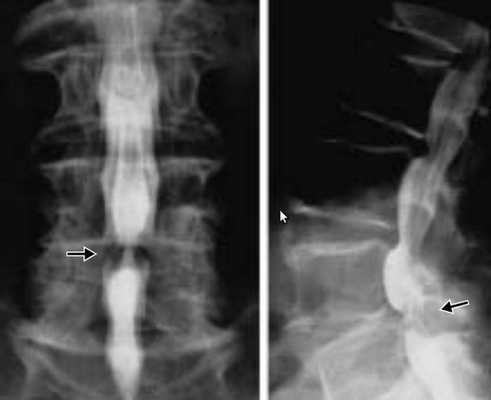

Диагностика стеноза позвоночного канала

Если появляются характерные жалобы, необходимы дополнительные методы обследования, которые позволят не только измерить размеры позвоночного канала, но и выявить причины, вызывающие компрессию нервных элементов внутри позвоночного канала.

- рентгенография пояснично-крестцового отдела позвоночника;

- компьютерная томография (КТ);

- магнитно-резонансная томография (МРТ).

Позвоночный стеноз диагностируют по совокупности выявленных признаков сужения позвоночного канала при наличии характерных клинических данных.